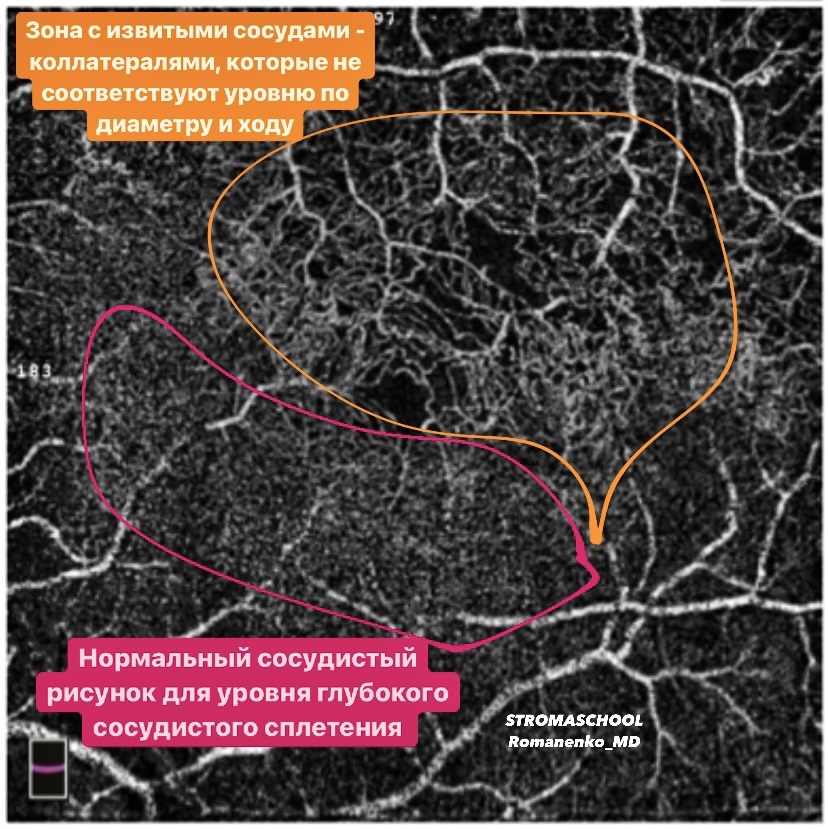

- все материалы (фото фундус камеры, сканы ОКТ взяты из личной практики и разобраны для Вас лично мной) - это ЧЕСТНО! А здесь только так!

- видео, сканы ОКТ с обозначениями, фото глазного с разбором на детали, аудисопровождение, текст и, конечно, ОБУЧАЩИЕ ТЕСТЫ